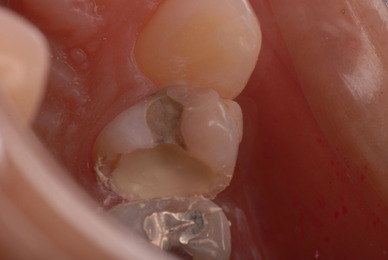

歯周病の疑いで東京のかなり遠方の方が来院されました。

驚くべきことですが、定期検診は受けていたそうです。しかしながら歯周病の指摘は受けたことがないそうです。

何故か?定期検診が虫歯のチェックのみになり、又肝心の歯周病の検査や歯周病の部分の予防や治療のためのブラシの使い方などを学んだ事がないのです。

本当に患者さんのことを考えると憂鬱になります。歯周病が悪化すると殆ど回復は無理だからです。

抜いてインプラントにすれば収入は増えるでしょうし入れ歯にしても幾らかの費用はいただけるでしょう。